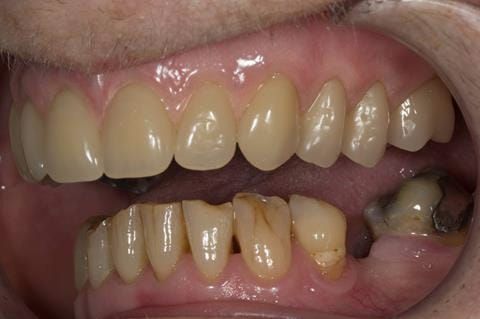

- Poorly fitting cobalt chromium based maxillary partial denture, which has been added to. This exhibited poor retention, stability and tissue fit (support). Unable to wear a new acrylic based denture.

- UR7 - occlusal amalgam. 10- 20% alveolar bone loss. Healthy periodontium with reduced attachment level. No mobility.

- Eight mandibular anterior teeth worn incisal edges from now extracted maxillary anterior crowns. Gingivitis - owing to inadequate oral hygiene.

- LL6 with large amalgam restoration - healthy periodontium.